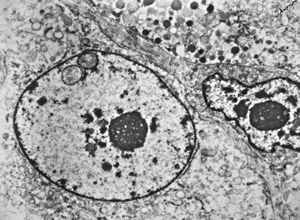

M,60y. | jejunum - amyloidosis